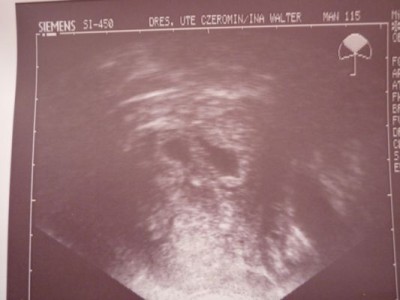

Will euch mal was zeigen :)

Dateianhänge

Unsere 2.jpg

@Leo: Ach einfach wunderschön so ein US-Bild, oder? Wie hast Du denn das hier reingestellt? Also eingescannt oder wie geht das?

@Kaninchen: Ja wie sehr man sich doch über so ein Bildchen freuen kann!

erstmal liebe @LEO-SYLVIA: Ich freue mich sehr für die schöne Fruchthöhle(n) und sei nicht traurig, das Herzchen bzw. die Herzchen schlagen ganz bestimmt schon nächste Woche. Aber kann Dich gut verstehen, es ist sicherlich erstmal entäuschend gewesen. Dei US-Bild sieht schön aus (willa auch!) und hier im Ordner ist wirklich eine Zwillingswelle (bei mir sicherlich nicht, kommt gleich). Ich denke, Justin freut sich über zwei Spielkameraden!!!! *g*